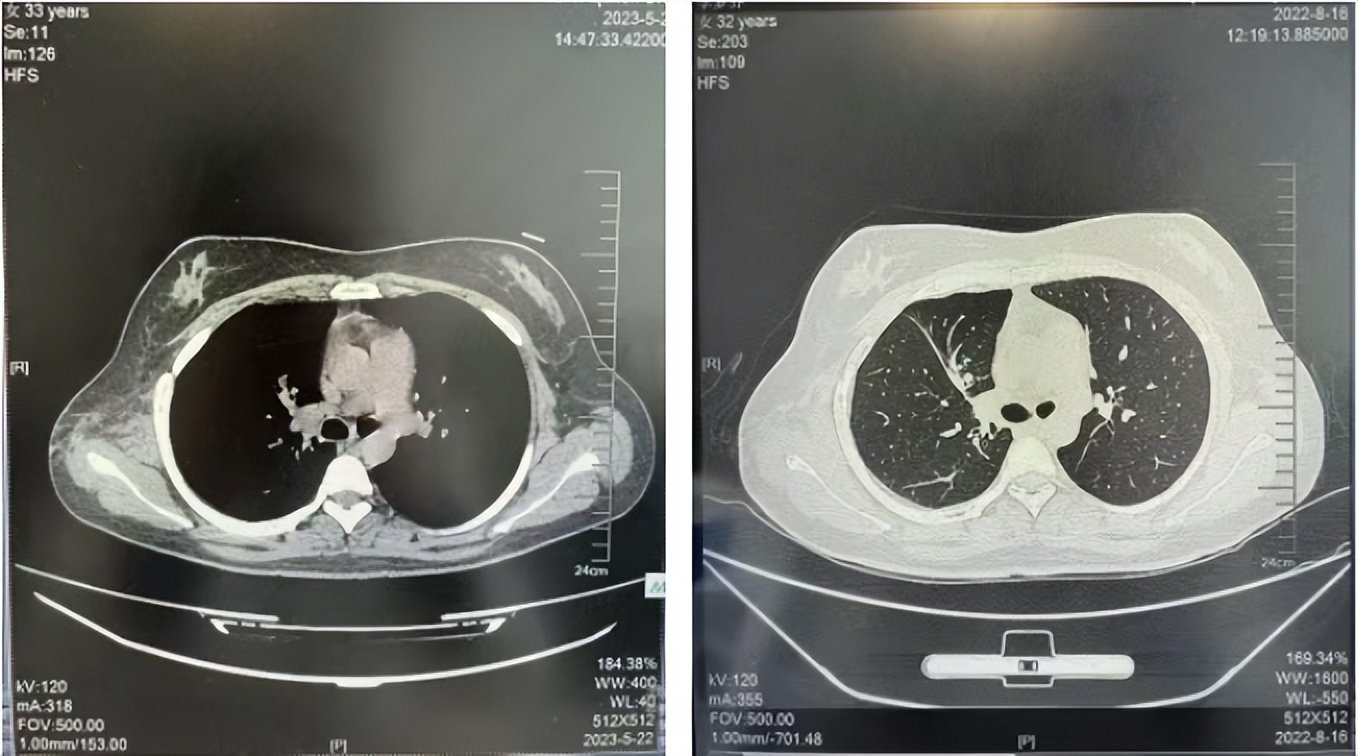

2016年1月复查CT提示支气管截断可见新发小结节,一线治疗采用培美曲塞+DDP方案化疗4周期(培美曲塞3.36,DDP 480mg)。化疗后复查胸部CT:右肺见不规则结节样影,最大层面大小约19mm*8mm,较前比较明显增大,疗效评估PD。2017.3-2017.4予单药多西他赛化疗3周期,疗效评估SD。2018年5月末复查CT提示结节较前增大,评效为PD,2018年6-10月予多西他赛+CBP化疗4周期,疗效评估SD。2022年5月患者出现活动后气短,复查胸部CT示右肺膨胀不良;右侧胸腔积液增多。胸腔积液包埋病理示符合肺腺癌细胞。行NGS基因检测:EML4:exon13-ALK:exon20融合。PD-L1(克隆号22C3)TPS<1%。

诊疗经过:2022年5月始口服克唑替尼3个月,出现肝功能异常(DILI 2级伴临床症状),改用恩沙替尼靶向治疗至今,目前评效为维持PR。恩沙替尼应用期间出现轻度肝功能异常(DILI 1级),对症处理后好转。截止目前PFS 33个月。

2022.08

2023.05